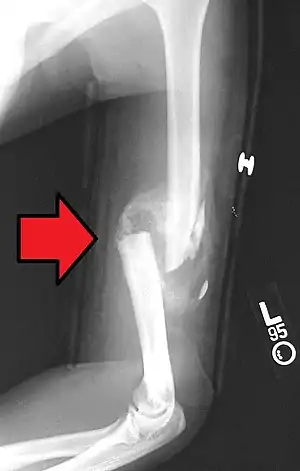

Proximal humerus fracture A transverse fracture of the humerus shaft

A transverse fracture of the humerus shaft A spiral fracture of the distal one-third of the humerus shaft